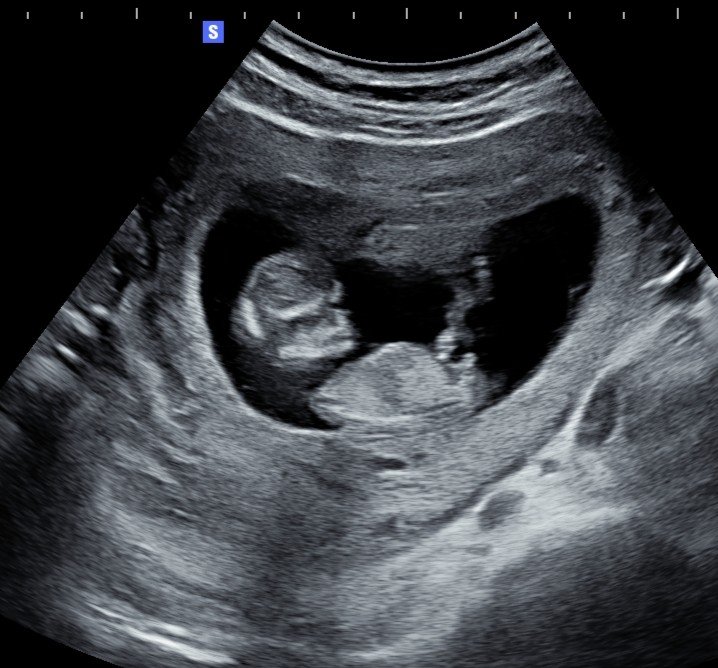

Lo ideal es entre la semana 24 y 30, ya que el bebé tiene un tamaño y desarrollo óptimos para obtener imágenes claras y detalladas.

Sí, contamos con experiencia en ecografías de embarazos gemelares y adaptamos la sesión para ambas imágenes se vean con la mejor calidad posible.